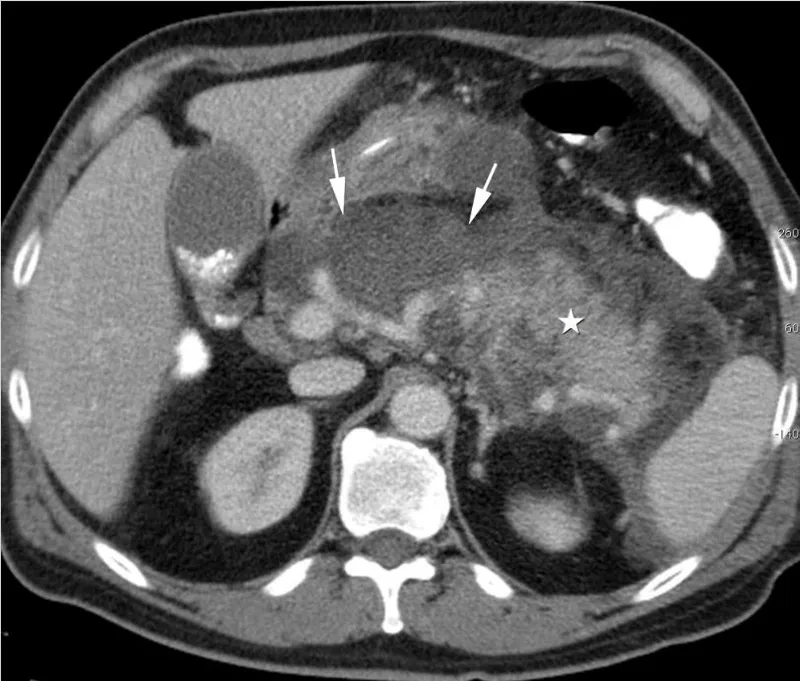

- Complications: Pseudocyst, abscess, necrosis, ARDS, renal failure.

Pancreatic Ductal Adenocarcinoma (PDAC): Most common, aggressive malignancy.

- Presentation: Late; often unresectable.

- Head (~75%): Painless obstructive jaundice, weight loss, steatorrhea.

- Body/Tail: Abdominal pain radiating to the back, weight loss.

- Pancreatic pseudocysts are a hallmark complication of acute pancreatitis, lacking a true epithelial lining.